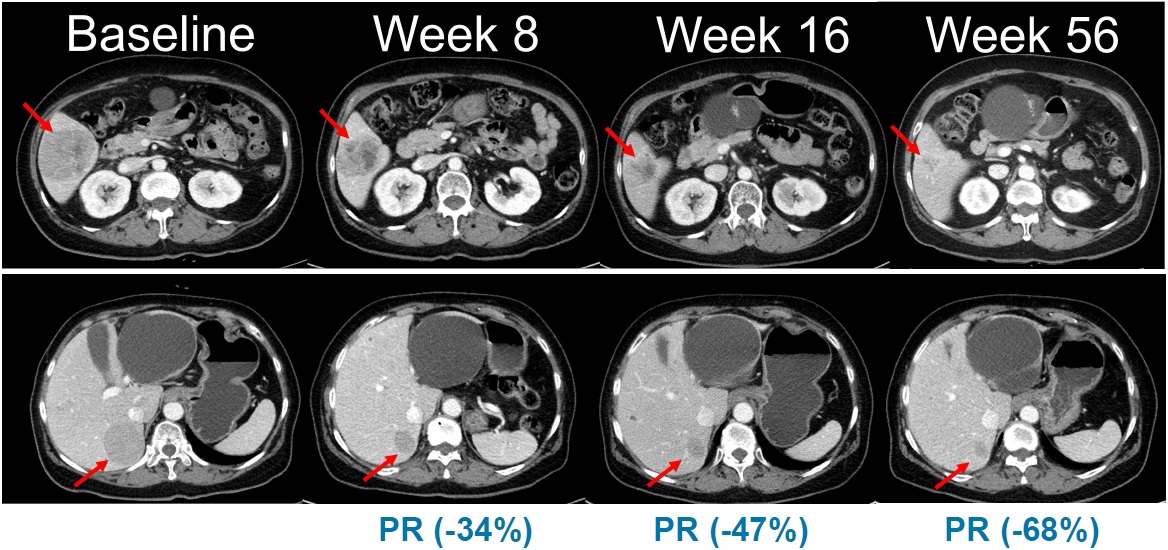

'리브리반트', 폐암 이어 두경부암에서도 새 가능성 확인[데일리팜=손형민 기자] '리브리반트'가 비소세포폐암을 넘어 두경부 편평상피세포암(HNSCC) 영역에서도 의미있는 가능성을 보여주고 있다. 특히 리브리반트가 효과를 보인 인유두종바이러스(HPV) 비관련 환자군은 치료 옵션이 제한적이었던 만큼 새로운 표적 치료제에 대한 수요가 높아 임상적 기대가 커지고 있다. 21일 관련 업계에 따르면 미국 식품의약국(FDA)은 최근 '리브리반트 파스프로(Rybrevant Faspro, 아미반타맙)'를 혁신치료제(BTD)로 지정했다. 주요 적응증은 HPV 비관련 진행성 두경부암이다. 리브리반트는 완전 인간 유래 이중특이항체로, 활성 EGFR 변이와 MET 변이·증폭을 함께 억제해 종양 성장 경로를 근본적으로 차단한다. 특히 리간드 결합 차단과 수용체 분해 촉진을 통해 EGFR 변이 폐암에서 관찰되는 다양한 저항성 경로를 포괄적으로 억제하는 점이 특징이다. 현재 리브리반트는 비소세포폐암 치료제로 주요 국가에 허가돼 있다. 두경부 편평상피세포암은 전 세계 암 발생의 약 4.5%를 차지하는 고형암으로 흡연·음주 등과 연관된 HPV 비관련 유형이 약 75%를 구성한다. 이 유형은 치료 반응률이 낮고 치료 저항성이 높아 면역항암제 단독요법의 반응률도 18% 안팎에 그친다. 이러한 치료 환경을 고려할 때 주요 성장·저항성 경로인 EGFR과 MET을 동시에 겨냥하는 접근법의 필요성이 꾸준히 제기돼 왔다. 다만 기존 리브리반트의 경우 3주에 1번 병원에 방문해 투여받아야 하는 정맥주사(IV) 제형이다. 이에 환자들의 투여 편의성이 저해될 수 있다는 점이 지적됐다. 이에 얀센은 리브리반트 SC 제형을 개발해 임상에 적용했다. 항암제 SC 제형은 10분 내외로 투여가 가능해 환자의 투약 시간을 대폭 줄일 수 있다는 강점이 있다. 이번 리브리반트 파스프로의 혁신치료제 지정은 임상1b/2상 OrigAMI-4 연구에서 관찰된 고무적 성과가 근거가 됐다. 연구에 참여한 38명의 평가 가능 환자에서 리브리반트 파스프로군의 전체반응률(ORR)은 45%였으며, 반응지속기간(DOR)은 7.2개월로 보고됐다. 8.3개월의 추적기간 동안 82%의 환자에서 종양 크기 감소가 확인됐다. 무진행생존기간(PFS)은 6.8개월, 전체생존기간(OS)은 아직 중앙값에 도달하지 않은 것으로 집계됐다. 안전성 측면에서 이상반응은 기존 리브리반트 연구들과 유사한 프로파일을 유지했다. 주요 리브리반트 파스프로의 이상반응은 피로(31%), 저알부민혈증(31%), 구내염(23%) 등이 흔한 부작용으로 나타났으며, IV 제형의 약점으로 지적된 주입관련반응(IRR)은 7%로 모두 1~2등급이었다. 치료 관련 이상반응으로 약물을 중단한 환자는 2%에 불과했다. 키트루다와 병용 가능성도 확인 리브리반트는 면역항암제 '키트루다(펨브롤리주맙)'와의 병용 가능성도 확인되고 있다. 최근 미국에서 개최된 2026 다학제 두경부암 심포지엄(MHNCS)에서는 리브리반트 파스프로를 키트루다와 병용한 OrigAMI-4 코호트 2 결과가 발표돼 관심을 모았다. HPV 비관련·PD-L1 양성 재발·전이 환자 39명을 대상으로 한 이 연구에서 병용요법의 ORR은 56%, 완전반응(CR)은 10%, 임상혜택률(CBR)은 74%로 나타났다. 종양 축소도 82%에서 확인됐고, 반응 도달까지 걸린 시간은 중앙값 9.7주였다. 10.4개월의 중간 추적 시점에서 46%가 치료를 유지하고 있었으며, PFS는 7.7개월로 나타났다. 이상반응은 발진, 조갑주위염, 저알부민혈증 등이 흔했으나 대부분 관리 가능한 수준이었다. 전문가들은 EGFR·MET 저해 기반의 리브리반트와 면역항암제 병용 전략이 기존 PD-1 중심 치료에서 관찰되지 않았던 깊고 지속적인 반응을 유도할 수 있다는 점에 주목하고 있다. 조슈아 바우믈(Joshua Bauml) 존슨앤드존슨 부사장은 "역사적으로 낮은 반응률이 반복돼 온 두경부암 치료에서 이번 결과는 치료 패러다임 변화를 시사한다"며 "폐암에서 효과를 보인 리브리반트의 기전이 두경부암에서도 의미 있는 전환점을 만들 수 있다"고 말했다. 또 존슨앤드존슨은 임상3상 OrigAMI-5 연구를 통해 리브리반트+키트루다+카보플라틴 조합을 HPV 비관련 재발·전이성 두경부암 1차 치료제로 평가하고 있다.2026-02-21 06:00:44손형민 기자 -